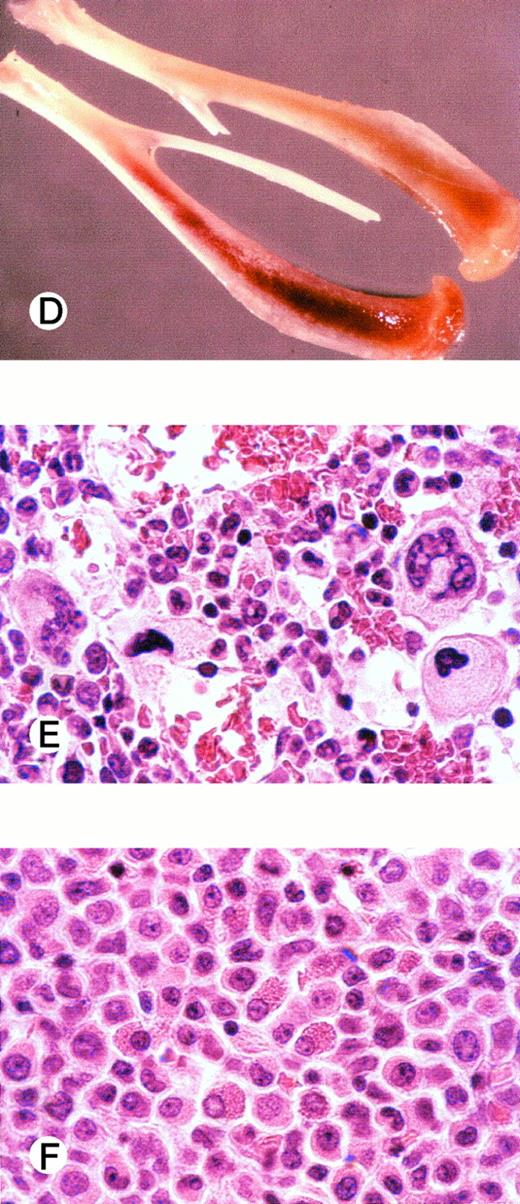

One highly engrafted animal was chosen for histological examination (Fig 3). Flow cytometric analysis showed high levels of human (CD45+ mCD18−) cells in both BM (88%, Fig 3A) and PB (92%, Fig 3C), whereas engraftment in the spleen was remarkably lower (15%, Fig 3B). Interestingly, the humerus of this animal appeared pale as compared with the humerus of an irradiated nontransplanted animal (Fig 3D). Confirming this observation at a histological level, examination of the humerus showed the presence of a solid mass of mostly undifferentiated cells and the apparent absence of erythropoiesis (Fig 3F) as compared with an irradiated nontransplanted control (Fig 3E). Despite the marked reduction in BM erythropoiesis, the animal was not anemic (not shown) but did have an enlarged spleen (with a cellularity of 17 × 106cells; control spleens contained 7.4 × 106 cells). As detected by flow cytometry, the spleen contained mouse as well as human (glycophorin A+) erythrocytes. In the five animals studied that had more than 80% human cells in the BM, the average spleen cellularity was 2.3 ± 0.6-fold higher (P < .05) than in control animals. In other human-mouse xenotransplants, the presence of an enlarged spleen has been attributed to compensatory mouse hematopoiesis39 40 due to the replacement of endogenous hematopoiesis in the BM by the xenotransplant.

Flow cytometric analysis of (A) BM, (B) spleen, and (C) PB of an animal transplanted with 25 × 106G-CSF–mobilized human peripheral blood CD34+ cells. The percentage of human cells (CD45+ and mCD18−) is indicated in the graphs. The spleen of this animal was enlarged as compared with control (17 × 106v 5.4 × 106 cells). In (D), humerus of this animal (top) as compared with the humerus of an irradiated nontransplanted control animal (bottom). In (E) and (F), histology (hematoxylin and eosin stain) of the bone marrow of control and transplanted animal, respectively.